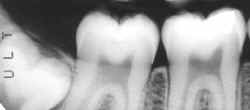

espaco2.gif (821 bytes)Radiografia da ossada

espaco2.gif (821 bytes)Região de molares inferiores direitos evidenciando perda provavelmente post-mortem dos dentes 47 e 48.

espaco2.gif (821 bytes)Observe que as formas alveolares e conseqüentemente das raízes perdidas estão evidentes.